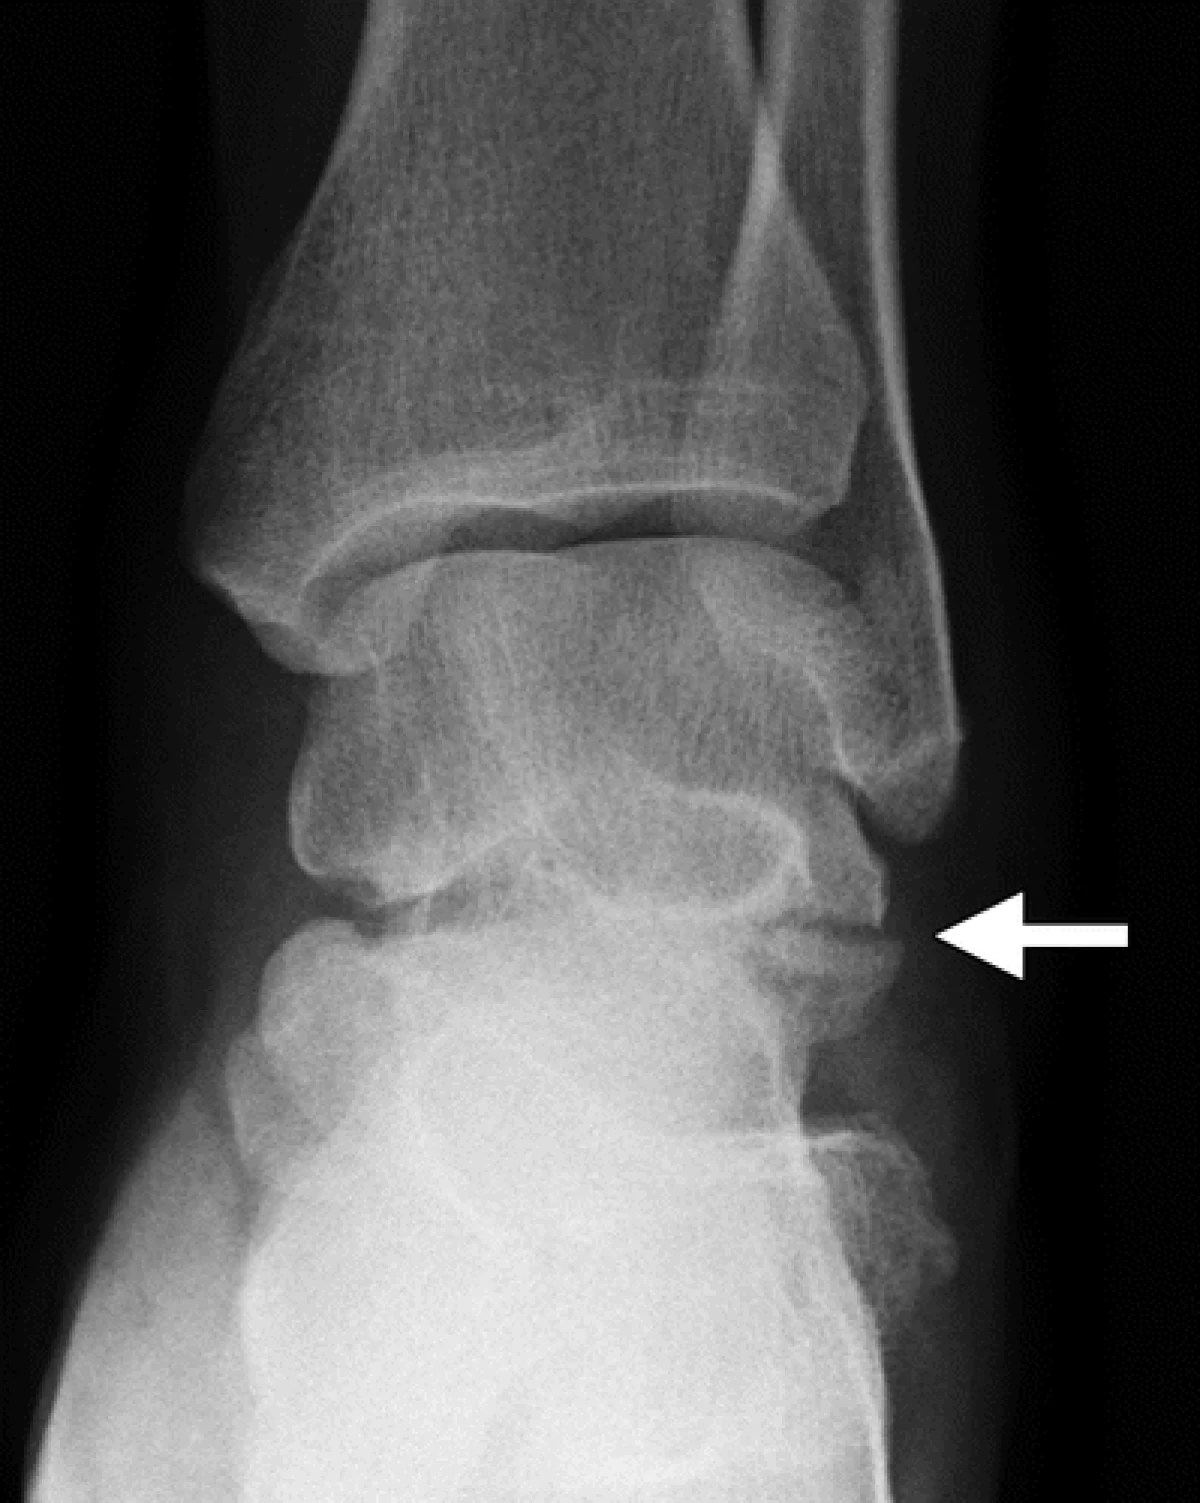

Lateral Talar Process Fractures FootEducation